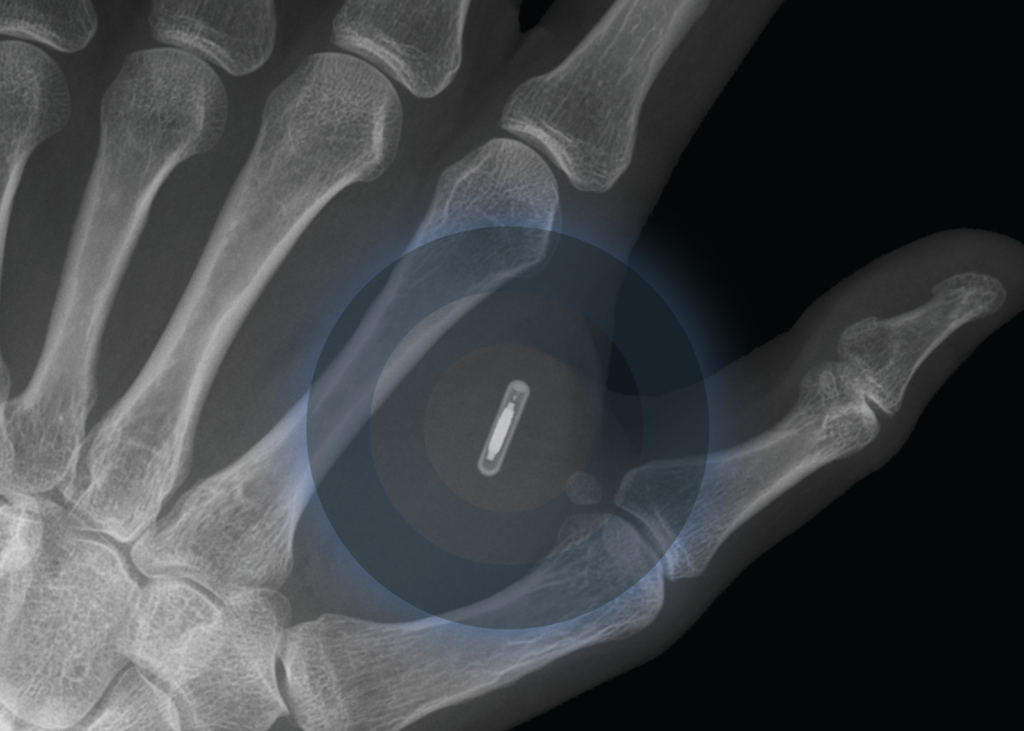

STOCKHOLM, Sweden (TND) — Microchip technology invented by Swedish startup company “Epicenter” is now being presented as a possible way to carry around a COVID-19 vaccine passport under a person’s skin, according to a viral video.

“Imagine showing your COVID-19 passport with just a flash of your arm,” the video says at its beginning, showing a person holding out their arm and scanning it with a mobile phone.